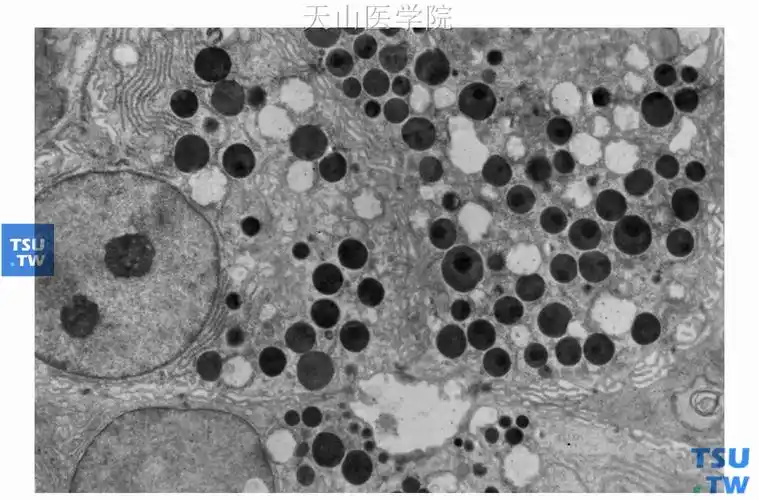

电镜下浆液性腺泡顶端充满分泌颗粒 ×14 000